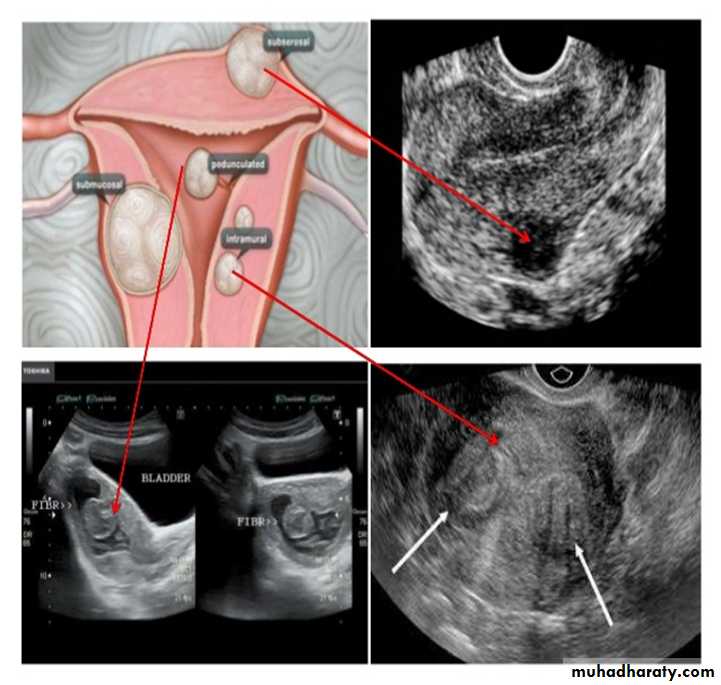

UUUUUUs of pelvic organs :

Ovarian cysts :

Ovarian cysts are commonly encountered in gynecological imaging, and vary widely in etiology, from physiologic, to complex benign, to neoplastic.Small cystic ovarian structures should be considered normal ovarian follicles unless the patient is pre-pubertal, post-menopausal, pregnant, or the mean diameter is >3.0 cm

Radiographic features

Ultrasound is usually the first imaging modality for assessment of ovarian lesions. Simple ovarian follicular cysts are: